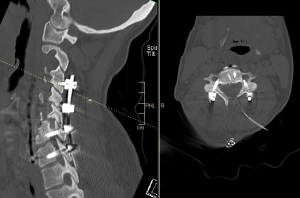

Ο απεικονιστικός έλεγχος με μαγνητική και αξονική τομογραφία της σπονδυλικής στήλης ανέδειξε εικόνα σωματεκτομής Α5, Α6 και μερικώς και Α7. Υπήρχε χαλάρωση των βιδών που καθήλωναν την πλάκα. Συνολικά εικόνα ψευδάρθρωσης και πίεσης επί του νωτιαίου μυελού και των αυχενικών ριζών (κυρίως Α7 δεξιά)

Διενεργήθηκε αρχικά οπίσθια σπονδυλοδεσία με διαυχενικές βίδες Α4, βίδες στα πλάγια ογκώματα Α5 και διαυχενικές βίδες Α7 και Θ1 ενώ έγινε και τρηματεκτομή Α6/7 δεξιά.

Στη συνέχεια, αφαίρεση της πρόσθιας πλάκας, ολοκλήρωση της σωματεκτομής Α5 & Α6, απελευθέρωση του νωτιαίου μυελου, πρόσθια δισκεκτομή Α7/Θ1 και τοποθέτηση πρόσθιας πλάκας Α4-Θ1.

Αρχικά έγινε οπίσθια σπονδυλοδεσία προκειμένω να στηριχθεί ο αυχένας της ασθενούς και να μειωθούν τα άλγη τα οποία οφείλονταν στην “αστάθεια” της αυχενικής μοίρας. Παράλληλα, διενεργήσαμε και οπίσθια τρηματεκτομή ώστε να εξασφαλίσουμε την απελευθέρωση της δεξιάς Α7 ρίζας, η οποία δημιουργούσε πόνο στην ασθενή. Όπως φαίνεται στη μετεγχειρητική αξονική τομογραφία, οι βίδες στους αυχένες του Α4 σπονδύλου τοποθετήθηκαν με ακρίβεια χιλιοστού. Σ’ αυτό, σημαντική ήταν η βοήθεια του διεγχειρητικού νευροπλοηγού σπονδυλικής στήλης με το πιο σύγχρονο σύστημα απεικόνισης (Ο-arm II)

Στη συνέχεια γυρίσαμε την ασθενή σε ύπτια θέση και αφού αφαιρέσαμε την παλαιά πλάκα, αποκαθηλώνοντας τον οισοφάγο, ολοκληρώσαμε τη σωματεκτομή και απελευθερώσαμε τα νευρικά στοιχεία και από μπροστά. Μια και δεν ήταν δυνατή η στήριξη της πλάκας στον Α7, αλλά ούτε και θέλαμε να καταλήξουμε ένα τεράστιο χάσμα, αποφασίσαμε να διατηρήσουμε τον Α7 και να διενεργήσουμε πρόσθια δισκεκτομή Α7/Θ1, καθηλώνοντας τελικά την πλάκα στον Α4, Α7 και Θ1 σπόνδυλο.